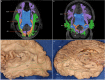

The human inferior longitudinal fasciculus (ILF) is a ventral, temporo-occipital association tract. Though described in early neuroanatomical works, its existence was later questioned. Application of in vivo tractography to the neuroanatomical study of the ILF has generally confirmed its existence, however, consensus is lacking regarding its subdivision, laterality and connectivity. Further, there is a paucity of detailed neuroanatomic data pertaining to the exact anatomy of the ILF. Generalized Q-Sampling imaging (GQI) is a non-tensor tractographic modality permitting high resolution imaging of white-matter structures. As it is a non-tensor modality, it permits visualization of crossing fibers and accurate delineation of close-proximity fiber-systems. We applied deterministic GQI tractography to data from 30 healthy subjects and a large-volume, averaged diffusion atlas, to delineate ILF anatomy. Post-mortem white matter dissection was also carried out in three cadaveric specimens for further validation. The ILF was found in all 60 hemispheres. At its occipital extremity, ILF fascicles demonstrated a bifurcated, ventral-dorsal morphological termination pattern, which we used to further subdivide the bundle for detailed analysis. These divisions were consistent across the subject set and within the atlas. We applied quantitative techniques to study connectivity strength of the ILF at its anterior and posterior extremities. Overall, both morphological divisions, and the un-separated ILF, demonstrated strong leftward-lateralized connectivity patterns. Leftward-lateralization was also found for ILF volumes across the subject set. Due to connective and volumetric leftward-dominance and ventral location, we postulate the ILFs role in the semantic system. Further, our results are in agreement with functional and lesion-based postulations pertaining to the ILFs role in facial recognition.